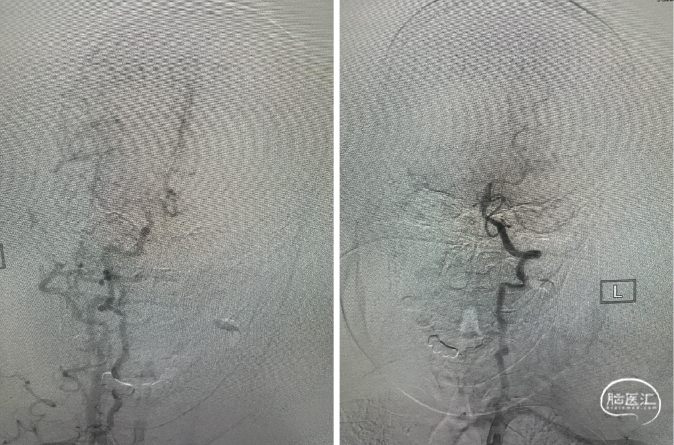

确认真腔:

0.014in Synchro携带Trevo Pro18微导管上到左侧大脑中动脉上干M2段,微导管造影,确认真腔。

SWIM技术取栓:

SWIM取栓后,血管再通,无栓子逃逸,闭塞局部无血管狭窄。